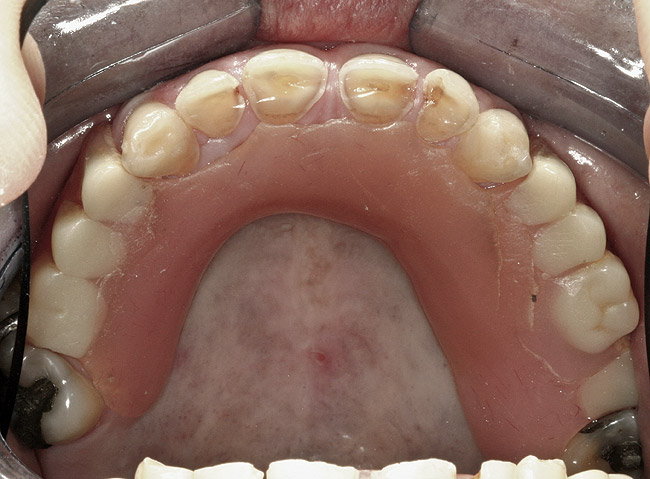

Figure 4  Intraoral occlusal view of maxillary dentition presenting excessive signs of wear.

Figure 4

Initial examination revealed a partial edentulous patient with extensive wear of the maxillary anterior teeth and moderate wear in the mandibular teeth (Figure 1, Figure 2, Figure 3 , Figure 4, Figure 5, Figure 6 and Figure 7). The patient's maxillary and mandibular RPDs also showed excessive wear and multiple signs of fractures (Figure 2 and Figure 3). The patient had been wearing a mandibular nightguard for 8 years.

A history of bruxing and consumption of acidic and carbonated drinks were reported. The clinical examination revealed severe tooth wear extending to the cervical level of the palatal surfaces of the maxillary teeth in some areas. Therefore, TSL was diagnosed as being caused by a combination of attrition and erosion.